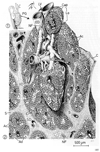

消化器;消化器系【しょうかきけい】(栄養分を取りこむ器官系で、言い換えれば、身体の成長に必要な物質と身体の活動を支えるためのエネルギー源とを取り入れるのが消化器の役割である。消化器は口腔・咽頭・食道・胃・小腸・大腸などから構成された「消化管」とこれに開く唾液腺・肝臓・膵臓などの「消化腺」とから出来ている。)